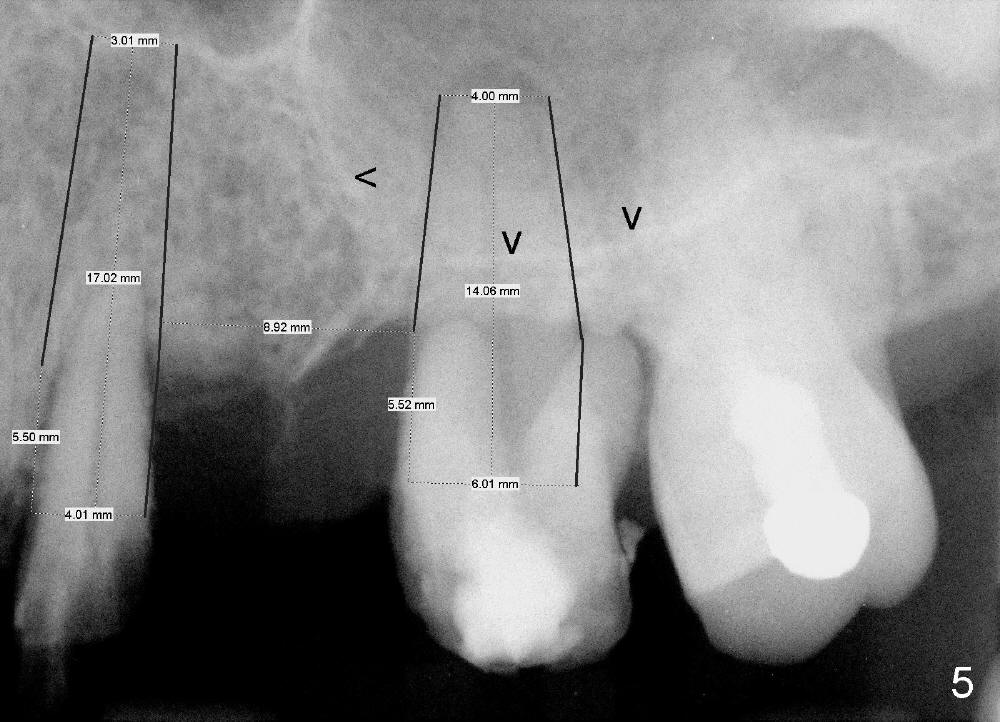

A 53-year-old lady has a failing bridge (Fig.1). There is severe bone loss around the buccal roots of #14 (*). Purulent discharge is from the gingival sulcus (Fig.2 <) with localized gingival erythema and edema (*). When the bridge is removed, the tooth #12 is found nonsalvageable (Fig.3,4). These two teeth are to be replaced by immediate implants (Fig.5). Although the sinus floor is low buccally (arrowheads), a 6x14 mm gingiva-level implant can be placed in the septum close to the palatal socket or in the palatal socket at the site of #14.

Initially the osteotomy is established with drill/reamers alternated with taps in the septum near the palatal socket. When a 4.5x14 mm tap (Fig.6 T; Fig.7: #14) is inserted, the sinus floor is perforated, but the sinus membrane is intact. When 7x14 mm tap is inserted, the sinus membrane is perforated in the buccal aspect of the osteotomy. The latter is repaired by placement of collagen dressing and then bone graft and membrane again (sandwich). The osteotomy is shifted to the palatal socket by using 5x14 and 6x14 mm taps. When the last tap is removed, the small area of the buccal aspect of the osteotomy is also found to be perforated, but the membrane is intact. When a 6x14 mm implant is placed (Fig.8), the coronal end is close to the middle of the socket (buccopalatally, due to angulation of the palatal socket).

Placement of immediate implant at the site of #12 is relatively easy. Adjustment is more or less mesiodistal. A 2 mm pilot drill (Fig.6 P) is found close to the root of the tooth #11 (red dashed line). The osteotomy is then moved distally (Fig.6 arrow). When 4.5x20 mm tap (Fig.7: #12) and 4.5x17 mm implant (Fig.8 I) are placed, there is distance from the root of the neighboring tooth. Insertion torque of the both implants is >60 Ncm. Abutments are placed (A in Fig.8) for immediate provisional.